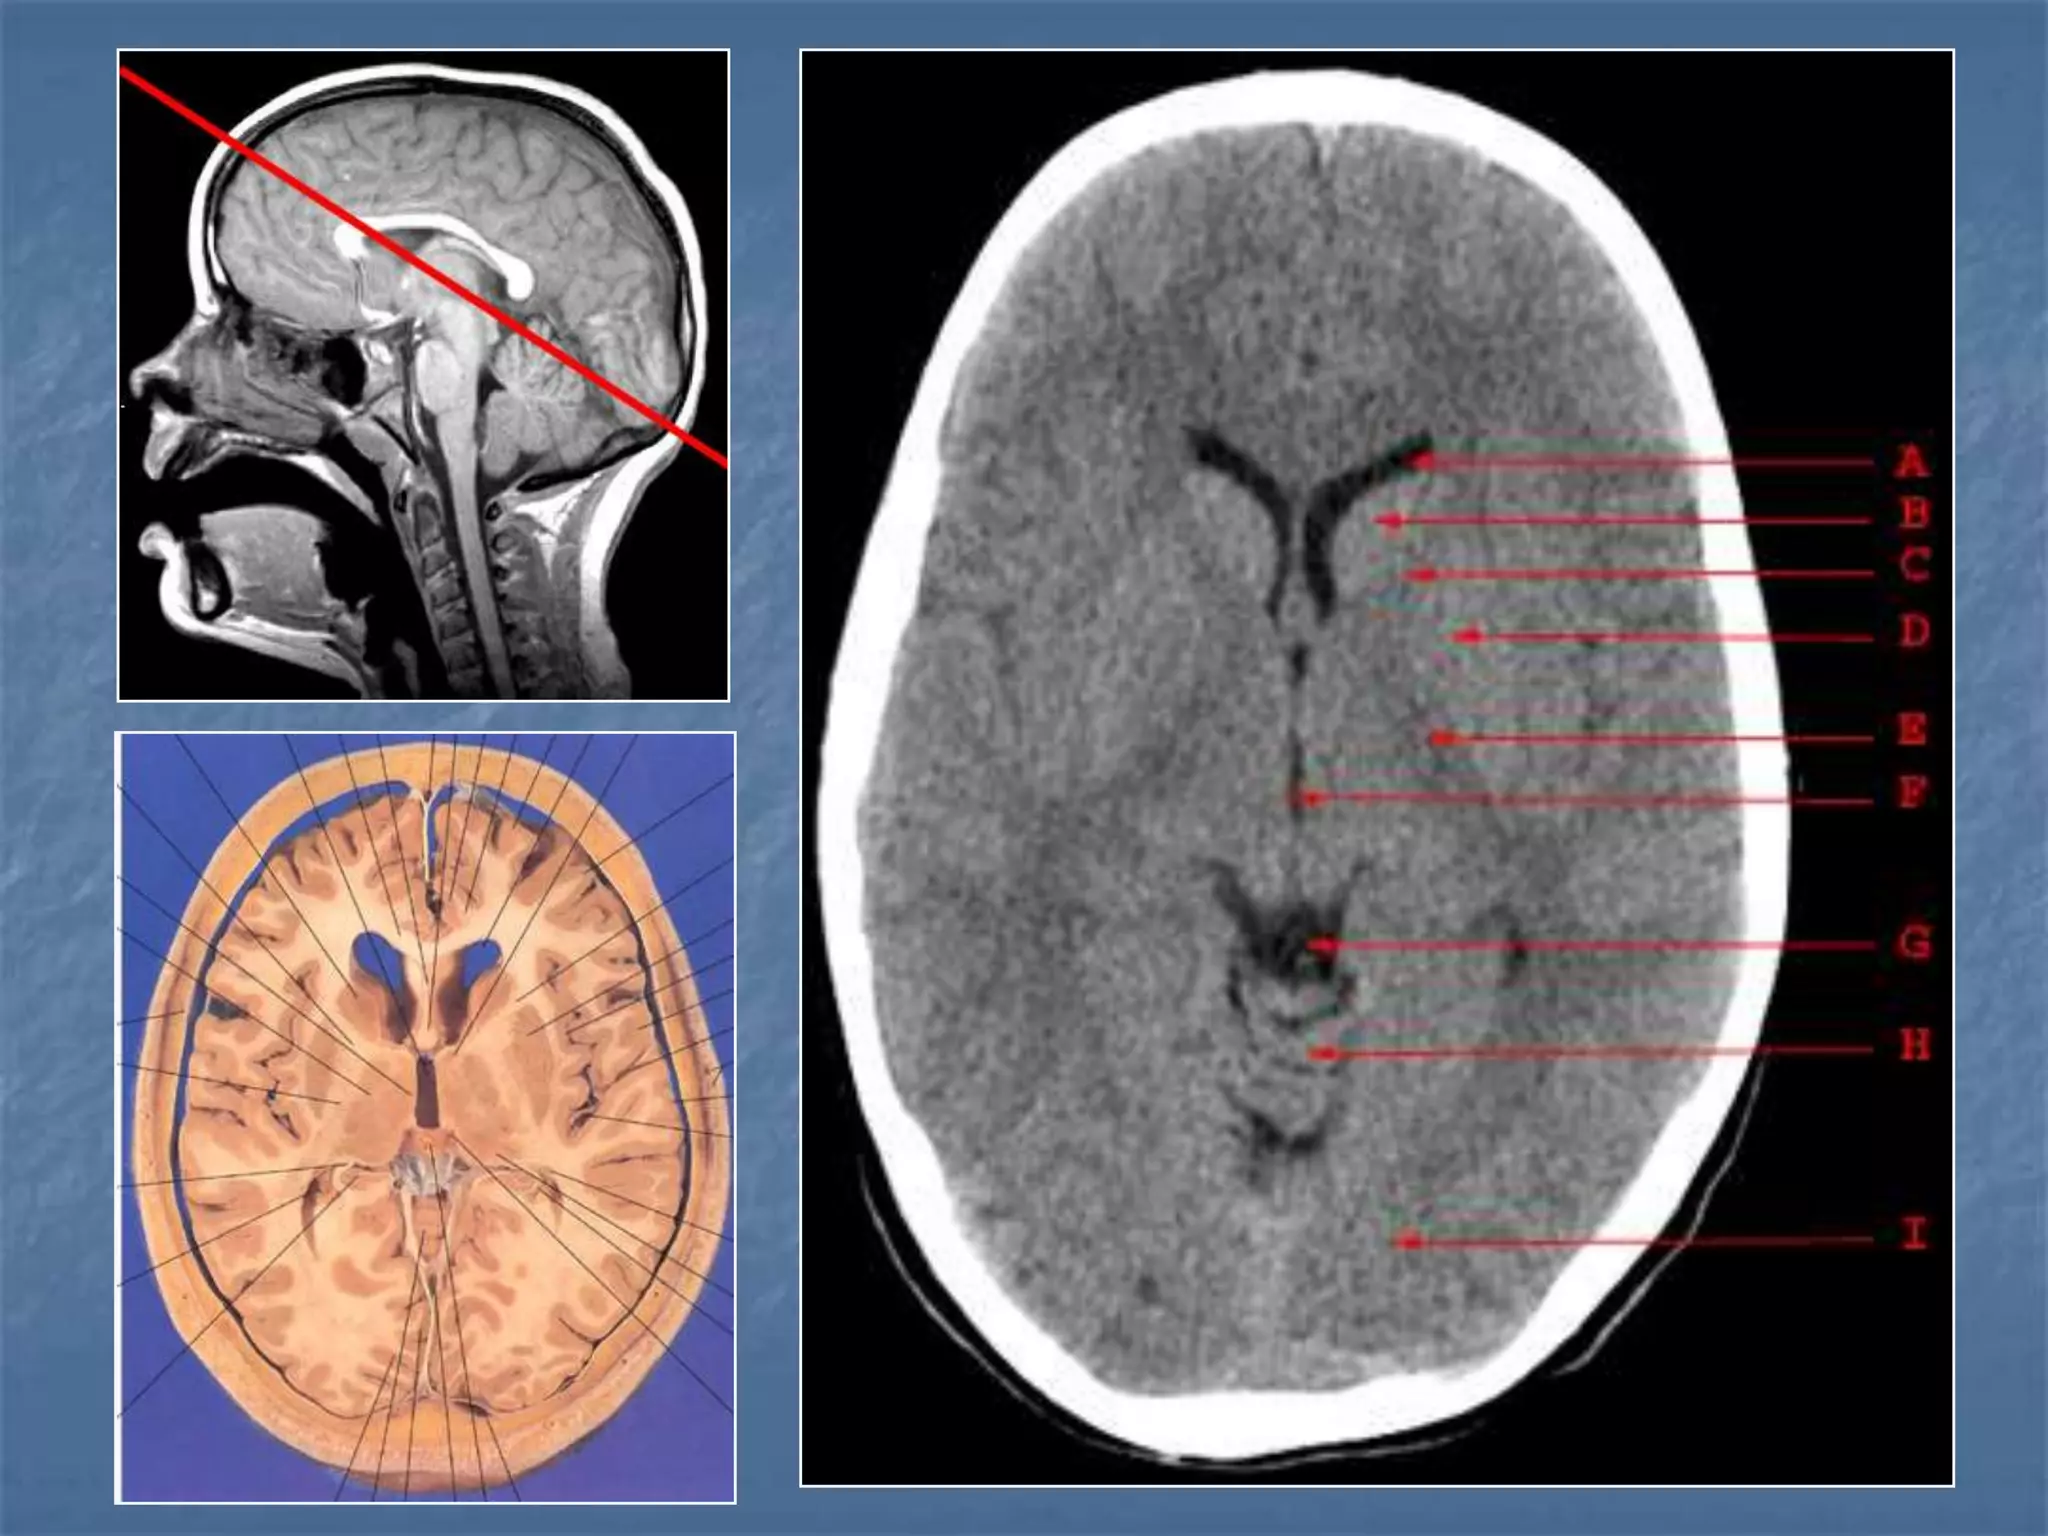

How the CT study is usually planned…

15-20 degree

angulation to

canthomeatal line

to decrease

radiation to the

lens.

 Thinner sections

are studied

through the

posterior fossa

Hounsfield Units

AIR - - 1000

FAT - - 30 to -100

CSF - 0

GREY MATTER - 32 - 41

WHITE MATTER - 23 - 34

ACUTE BLOOD - 56 - 76

CALCIFICATION - 60 - 400

BONE - 1000